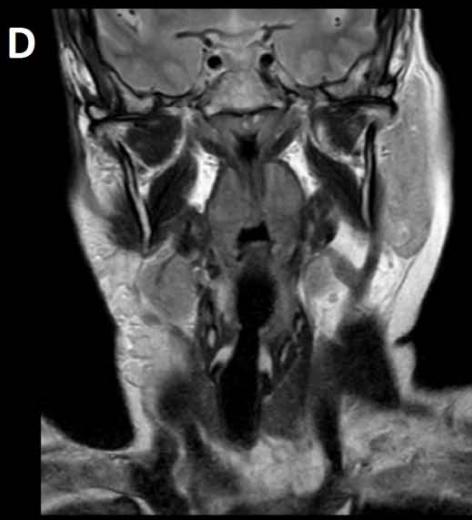

Figure/Patient 3

An 8 year-old girl with prior surgical excision of a right latero-cervical lymphangioma presenting with a new-onset tumefaction within the same region. MRI scans show a 9-10 cm subcutaneous multilocular lesion, extending between two virtual planes crossing the retro-molar trigone and the thyroid respectively, with deep invasion of parapharyngeal spaces cranially and the space between the submandibular gland and the vascular peduncle of the neck caudally. The lesion appears hyper-intense on T2 weighted scans with (A-B) and without (C-D) fat suppression, hypo-intense on T1 weighted scans with (E) and without (F) fat suppression and hyper-intense on DWI scans with high B values (G). Diagnosis of loco-regional recurrence of cystic lymphangioma is done.